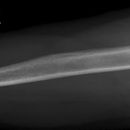

Oberarm lateral (2. Ebene)

Fraktureinteilung

der proximalen Humerusfrakturen (2) nach Neer (modifiziert):

Einteilung des Humeruskopfes in vier anatomische Segmente: Kopf, Tuberculum majus, Tuberculum minus, Schaft

- Typ I (85%): Jede Fraktur bei der keine Dislokation >1cm oder >45° vorliegt

- Typ II: Frakturen des Collum anatomicum (>1cm oder >45°); können bei inadäquater Aufnahmetechnik (Innenrotation!) leicht übersehen werden: GEFAHR der Humeruskopfnekrose!

- Typ III: Fraktur im Collum chirurgicum (>1cm oder >45°)

- bei Typ IV: Dislozierte Frakturen des Tuberculum majus gehen immer mit einer Rotatorenmanschettenruptur einher! Bei Abriss des Tuberculum maius rotiert das Kopfragment durch den Zug am Tuberculum minus (M. subscapularis) nach dorsal. Das abgerissene Tub majus disloziert durch den Zug der Außenrotatoren nach kranial und dorsal.

- Bei Typ V: bei Abriss des Tuberculum minus rotiert das Kopfragment durch den Muskelzug am Tub. maius (Außenrotatoren) nach ventral => "Vollmondzeichen", das abgerissene Tuberculum minus disloziert nach ventromedial.

- Bei Kindern regelhaft Epiphysenlösung, meist mit metaphysärem Fragment (Salter II)

der Humerusschaftfrakturen (2):

- Indirekte Gewalt => Spiralverletzung, Direkte => Quer-/Biegungs-/Stückfraktur

- In ca. 25% liegen Begleitverletzungen in der Schulter und des Unterarms vor! (Im mittleren Schaftdrittel: in 10% Radialisparesen)

- Frakturen proximal des Deltoideusansatzes: Dislokation des proximalen Fragments nach medial (Pektoraliszug), des distalen Fragments nach lateral (Deltoideuszug)

- Frakturen distal des Deltoideusansatzes: Dislokation des proximalen Fragments nach lateral (Zug des M. deltoideus und M.coracobrachialis), des distalen Fragments nach proximal (Zug des M. biceps und M. triceps)

der distalen Humerusfrakturen (vgl. Ellbogen):

- Bei Erwachsenen in 90% Gelenkbeteiligung

- Bei Kindern meist suprakondyläre Frakturen (Cave Knochenkerne!)

- Bei disloziertem Fragmentabscherungen am Capitulum humeri oder der Trachlea => „Halbmondzeichen“ durch konvexbogiges Fragment

- Verlagerung der ventralen und dorsalen Fettkörper (intraartikulär), Hämarthros